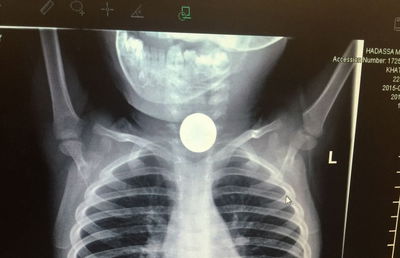

בתוך משמרת אחת בהדסה הר הצופים, שלושה מקרי בליעת חפצים מסכני חיים על ידי ילדים קטנים.

הפיסטוק, המטבע והסוללה – אותרו מיידית ונשלפו החוצה בהצלחה (בריאות)